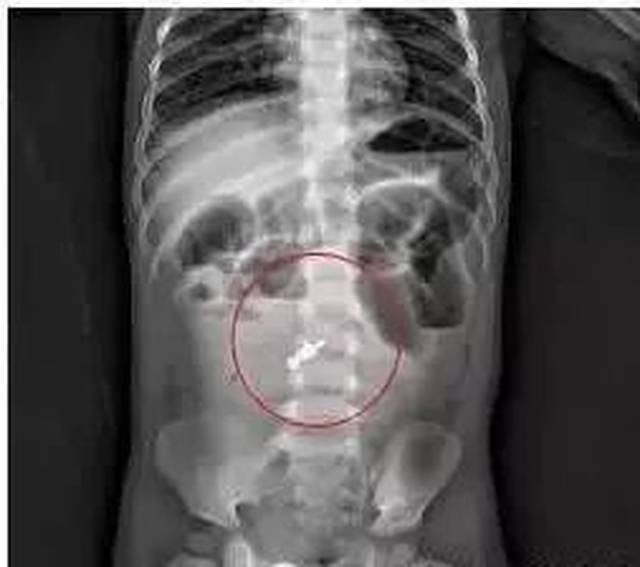

肠穿孔x线

肠穿孔x线,肠穿孔ct

肠穿孔的x线表现图片

肠穿孔腹部平片图片

腹部平片x线